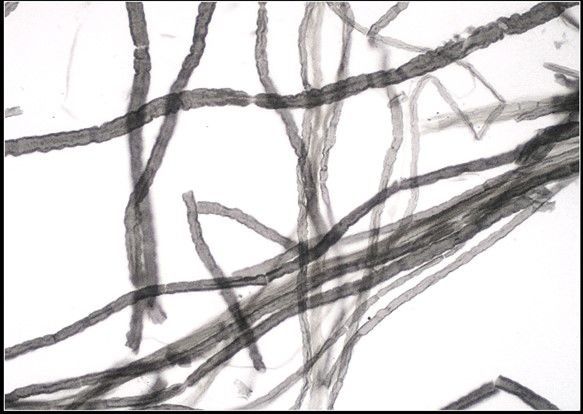

Question 9

Question

Label this Image First Dot: Name Second Dot: Staining

Image:

b80c15b7-511e-413d-b593-9847d29caf1b (image/jpeg)

Answer

Myelinated Nerve Fibers

OsO4